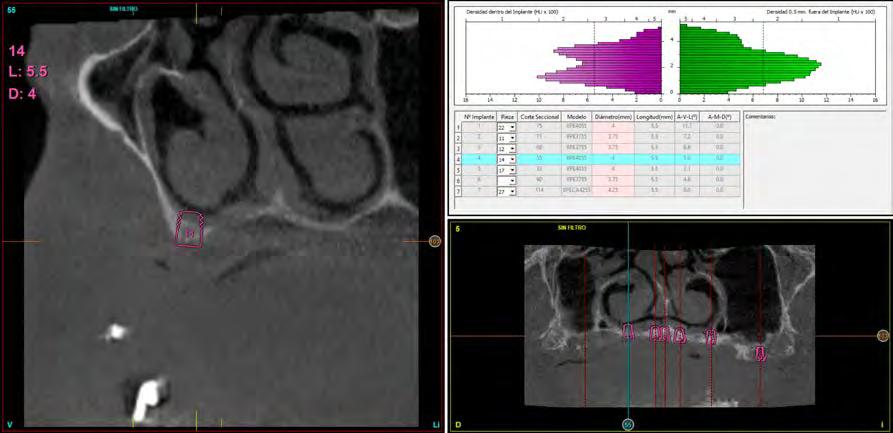

Figura 1. Diámetros y longitudes incluidos en el estudio según su posición.

Figura 2 y 3. Figuras intraorales del paciente de 67 años que acude a la consulta para rehabilitación sobre implantes superior, portador de una prótesis completa removible con una atrofia ósea evidente al ser la prótesis retirada. Figura 4. La radiografía inicial muestra una atrofia marcada en sentido vertical, que debe ser constatada posteriormente mediante un TAC así como para la planificación de la colocación de los implantes. Figura 5 y 6. Encerado diagnóstico para comenzar la planificación de la colocación de los implantes superiores guiados por la posición ideal que deben tener los dientes en la prótesis. De este encerado se realiza una guía radiológica que nos permita trasladar estas posiciones al TAC de planificación.

Fueron reclutados 6 pacientes en los que se colocaron 30 implantes para realizar rehabilitaciones completas. La edad media de los pacientes incluidos en el estudio fue de 66.75 años (+/- 5,16) y un 86.7% fueron mujeres. El 63.3% de los implantes se insertaron en el maxilar superior y el 36.7% restante en la mandíbula, formando parte de 4 rehabilitaciones

completas superiores y 3 inferiores. Todos los implantes presentaron una longitud de 5.5 m m, con diámetros comprendidos entre los 2.5 y los 5.5 mm. Las posiciones de los implantes corresponden a distribuciones biomecánicas para la realización de prótesis completas tanto en el maxilar como mandíbula (incisivos, premolares y molares). Los diámetros y longitudes de los implantes incluidos en el estudio en función de

181. Septiembre 2023 51 Rehabilitaciones completas implantosoportadas

su posición se muestran en la Figura 1.

Figura 7­9. Cortes de planificación del cone beam donde observamos la extrema atrofia vertical y la posición en la que deberían situarse los dientes con una gran discrepancia entre esta posición y la base ósea. Vemos también como se planifican implantes extracortos de 5.5 mm de longitud en todas las localizaciones. Figura 10. Radiografía panorámica tras la colocación de los implantes.

En las Figuras 2­17 se puede observar uno de los casos incluidos en el estudio.